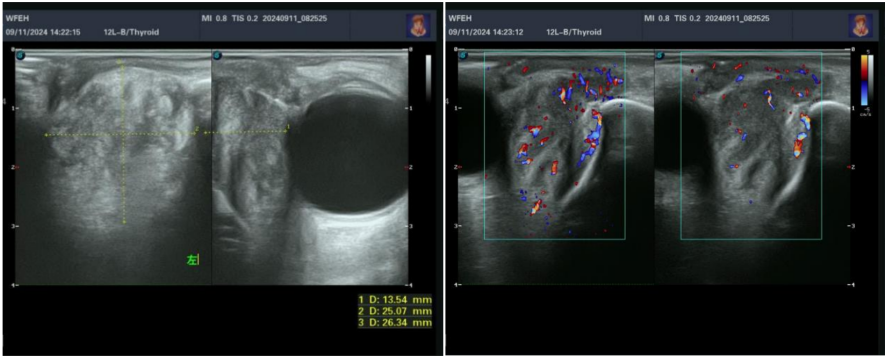

患者男,61岁,因左眼溢泪2个月于2024年9月16日入院。CT检查结果:1)左眼眶内肌锥外肿物,明显强化,考虑恶性肿瘤可能;2)双侧上颌窦炎、筛窦炎;3)左侧骨性鼻泪管扩张。查体:左内眦部下方隆起,扪及硬结,范围约2 cm×3 cm,边界不清,自泪囊区向眶内延续(图6)。泪道冲洗:经左眼上下泪小管冲洗全部对点反流。彩超检查结果:左眼泪囊显示不清,左眼眶内下方可见低回声区,范围约0.6 cm×0.5 cm×1.3 cm,边界不清,内回声不均匀,CDFI:内可见丰富血流信号(图7)。于2024年9月17日在全身麻醉下经皮肤切口联合鼻内镜入路行左眼眶泪道肿物切除术,术中见肿物无明显包膜,呈暗红色,质韧,与周围组织轻度粘连,周围临近软组织质韧;肿物向下附于内眦下方眶骨表面、与眶骨膜不易分离,向泪囊窝及眶内延续,与下斜肌起点处粘连,未累及内直肌、下直肌,将下斜肌起点附近骨膜连同肿物一起切除;鼻内镜下操作,见骨性鼻泪管骨质明显吸收,内壁可见鼻泪管暴露,去除骨性鼻泪管内侧壁、下鼻甲前端,见泪囊、鼻泪管膨大,易于剥离,将泪囊、鼻泪管及骨膜连同鼻泪管口附近部分鼻黏膜充分游离,经内眦切口将肿物摘除。标本巨检:泪囊鼻泪管膨大,呈暗红色,鼻泪管末端包含喇叭口样结构的下鼻甲下鼻道黏膜,大小约为4 cm×2 cm×2 cm。病理检查:(左眼眶肿物)恶性肿瘤,鼻泪管颞侧切缘未见恶性肿瘤;鼻泪管鼻侧切缘及泪囊部鼻侧切缘查见恶性肿瘤(图8)。免疫组化:CK(+)、CK5/6(+)、P40(+)、NUT(+)、P53(野生型)、Ki-67(+,50%)、CD56(局灶+)、CgA(-)、Syn(局灶+)、CD99(-)。诊断:(左眼眶肿物)低分化癌,结合形态及免疫组化,符合鼻窦NUT癌。确诊后嘱患者至综合医院肿瘤科进一步检查、治疗。患者回当地医院肿瘤科接受了化学治疗(具体方案不详),未再复诊。

图 7 一例泪道癌的眼眶彩超结果

Figure 7 Color doppler ultrasonography results of a case of lacrimal carcinoma

左眼泪囊显示不清,左眼眶内下方可见低回声区,大小约为2.6 cm×2.5 cm×1.3 cm,边界不清,内回声不均匀;彩色多普勒血流显像:内可见丰富血流信号。The left lacrimal sac is not clearly visualized. A hypoechoic area is seen inferiorly within the left orbit, measuring approximately 2.6 cm × 2.5 cm × 1.3 cm, with ill-defined borders and uneven internal echoes. Color Doppler flow imaging reveals abundant blood flow signals within the area.